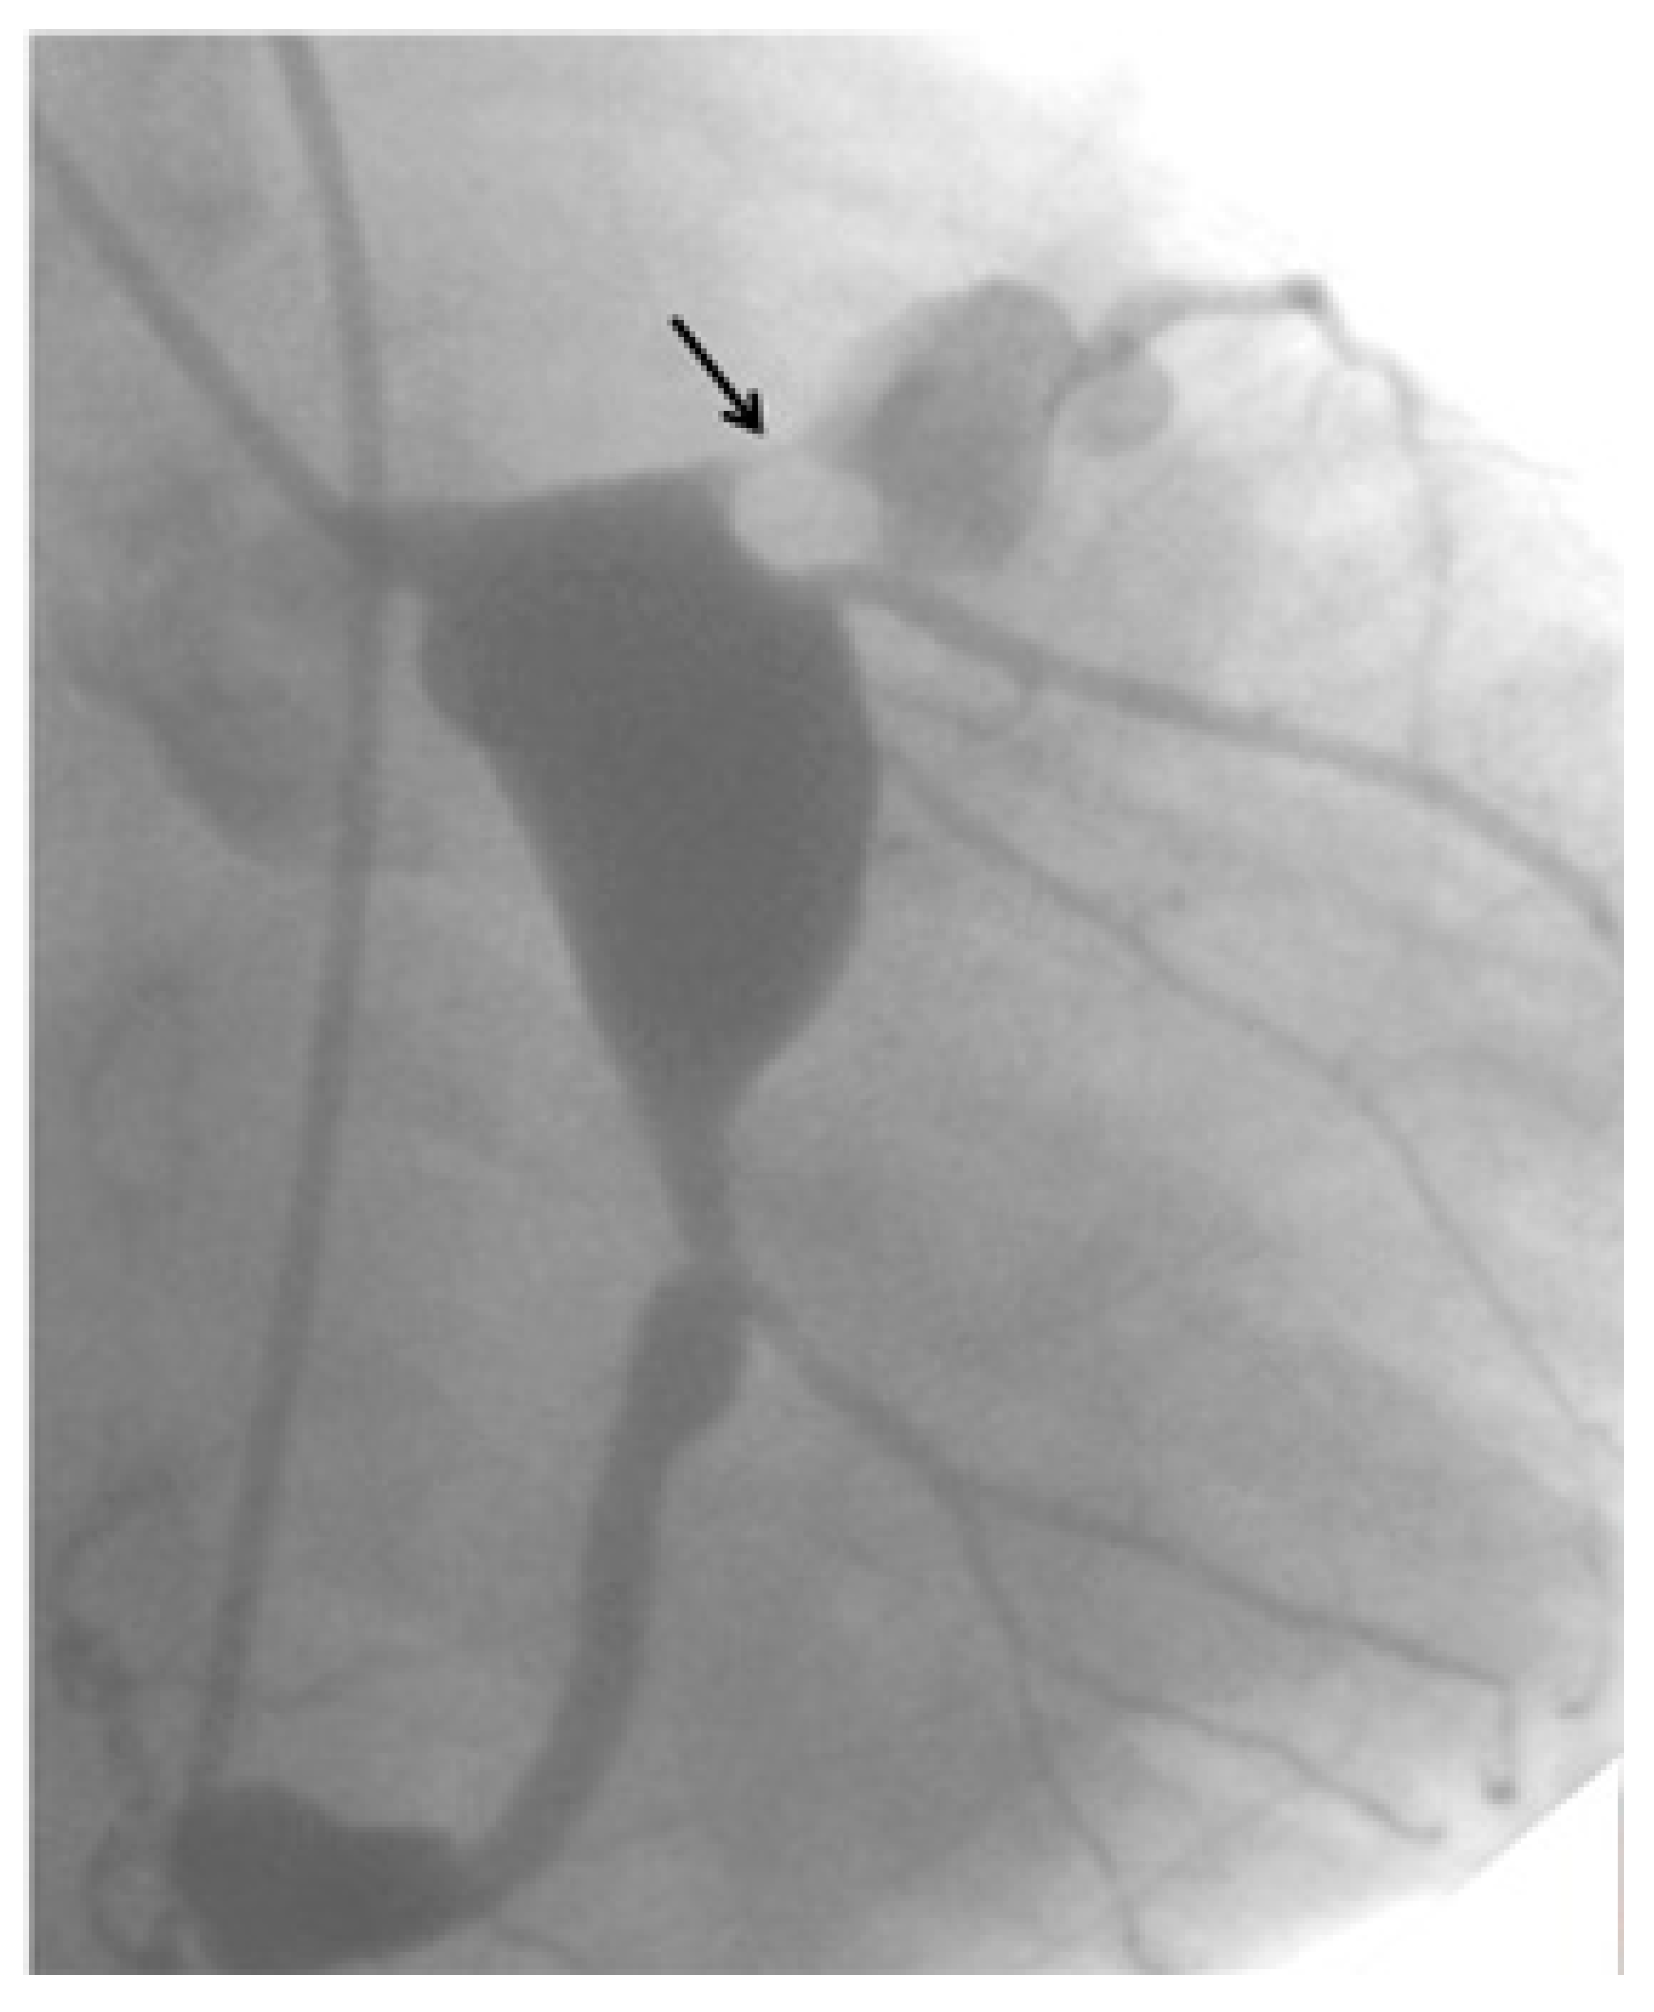

- Tsuda, E.; Fujita, H.; Yagihara, T.; Yamada, O.; Echigo, S.; Kitamura, S. Competition between native flow and graft flow after coronary artery bypass grafting. Impact on indications for coronary artery bypass grafting for localized stenosis with giant aneurysms due to Kawasaki disease. Pediatr. Cardiol. 2008, 29, 266–290. [Google Scholar] [CrossRef]